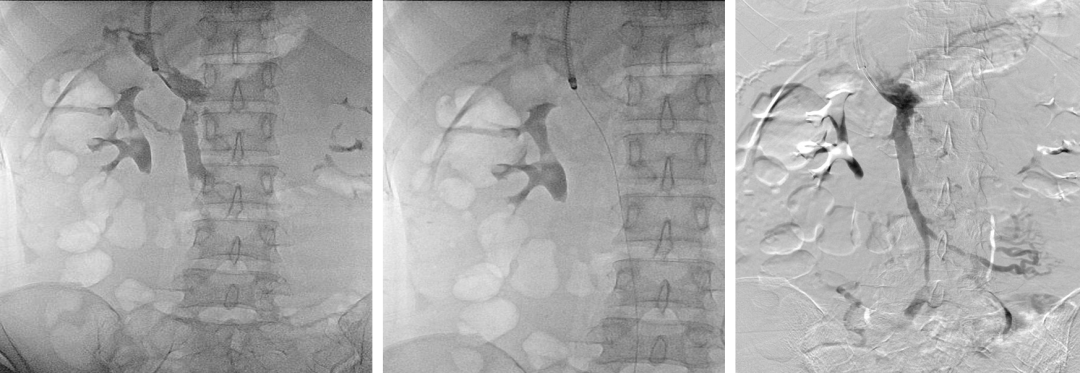

门静脉血栓(PVT)

联合使用 AngioJet、Straub 吸栓系统 经 TIPS 入路清除肠系膜上静脉血栓;

近年采用 Indigo 抽吸导管 成功处理肝移植术后门静脉血栓。

肝硬化门静脉血栓—TIPS联合AngoJet

肝硬化门静脉血栓—TIPS联合Straub吸栓

近期尝试Indigo抽吸导管用于肝移植术后门静脉血栓

门静脉海绵样变(CTPV)

2010年前多行脾肾分流等外科手术;

2012年后,通过精准穿刺仅存的门静脉主干,成功完成 TIPS,避免开腹。

慢性PVT(门静脉海绵样变)

TIPS治疗门静脉海绵样变